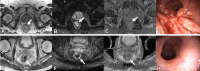

![Flowchart shows randomization of participants in the Organ Preservation in

Rectal Adenocarcinoma (OPRA) trial, inclusion and exclusion for the current

analysis, and a summary of characteristics for each restaging MRI-based response

category (clinical complete response [mr-cCR], near-complete clinical response

[mr-nCR], incomplete clinical response [mr-iCR]). * = b ≥ 800

sec/mm². DWI = diffusion-weighted imaging, TME = total mesorectal

excision, TNT = total neoadjuvant therapy, T2WI = T2-weighted

imaging.](https://cdn.ncbi.nlm.nih.gov/pmc/blobs/912d/11427875/7e15fb041759/radiol.232748.fig2.gif)